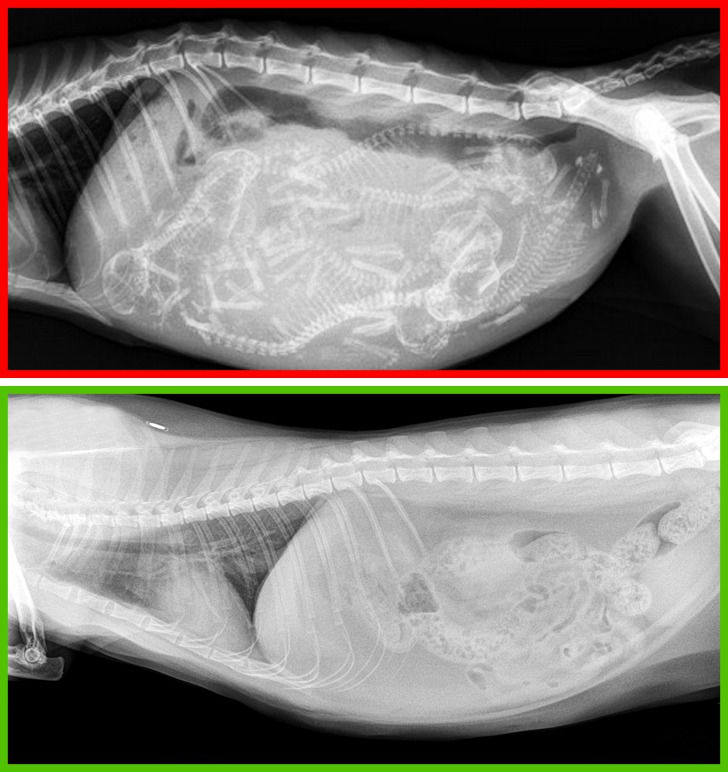

Upper photo: an X-ray image of a pregnant cat. Lower photo: an X-ray image of a spayed cat.

In most cases, these procedures have a positive impact on a cat’s health. They reduce the risk of mammary tumors in female cats and testicular tumors in male cats. Moreover, neutered cats aren’t prone to aggression or running away from home.